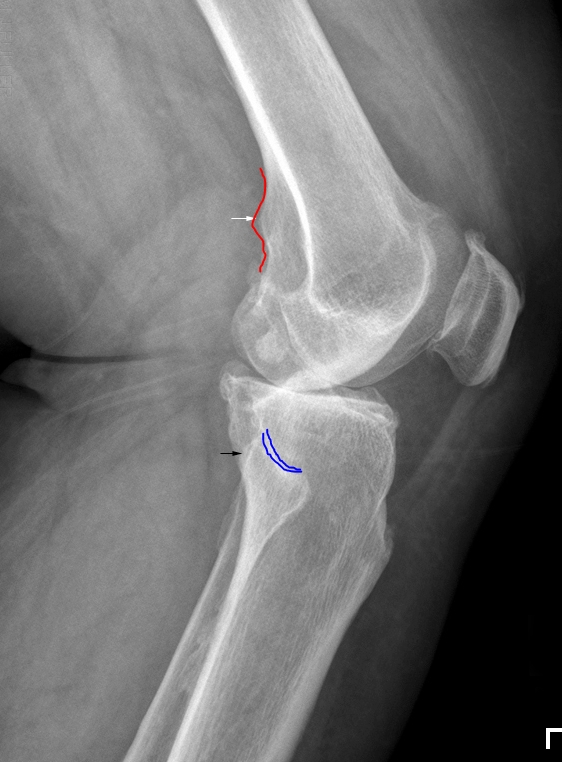

- 트루라테랄 촬영시 중요한점은 저 빨간선(adductor tubercle) 과 파란선(tibiofibula joint)이 포인트.

- adductor tubercle은 medial에 붙어있음.

- 좌측사진은 adductor tubercle이 안쪽 -> 다리를 충분히 돌리지 못한 사진

- 우측사진은 adductor tubercle이 바깥쪽 -> 다리를 과도하게 돌린 사진

- 좌측사진은 tibiofibula joint가 겹쳐서 보임. -> 다리를 충분히 돌리지 못한 사진

- 우측사진은 tibiofibula joint가 활짝 열려보임. -> 다리를 과도하게 돌린 사진